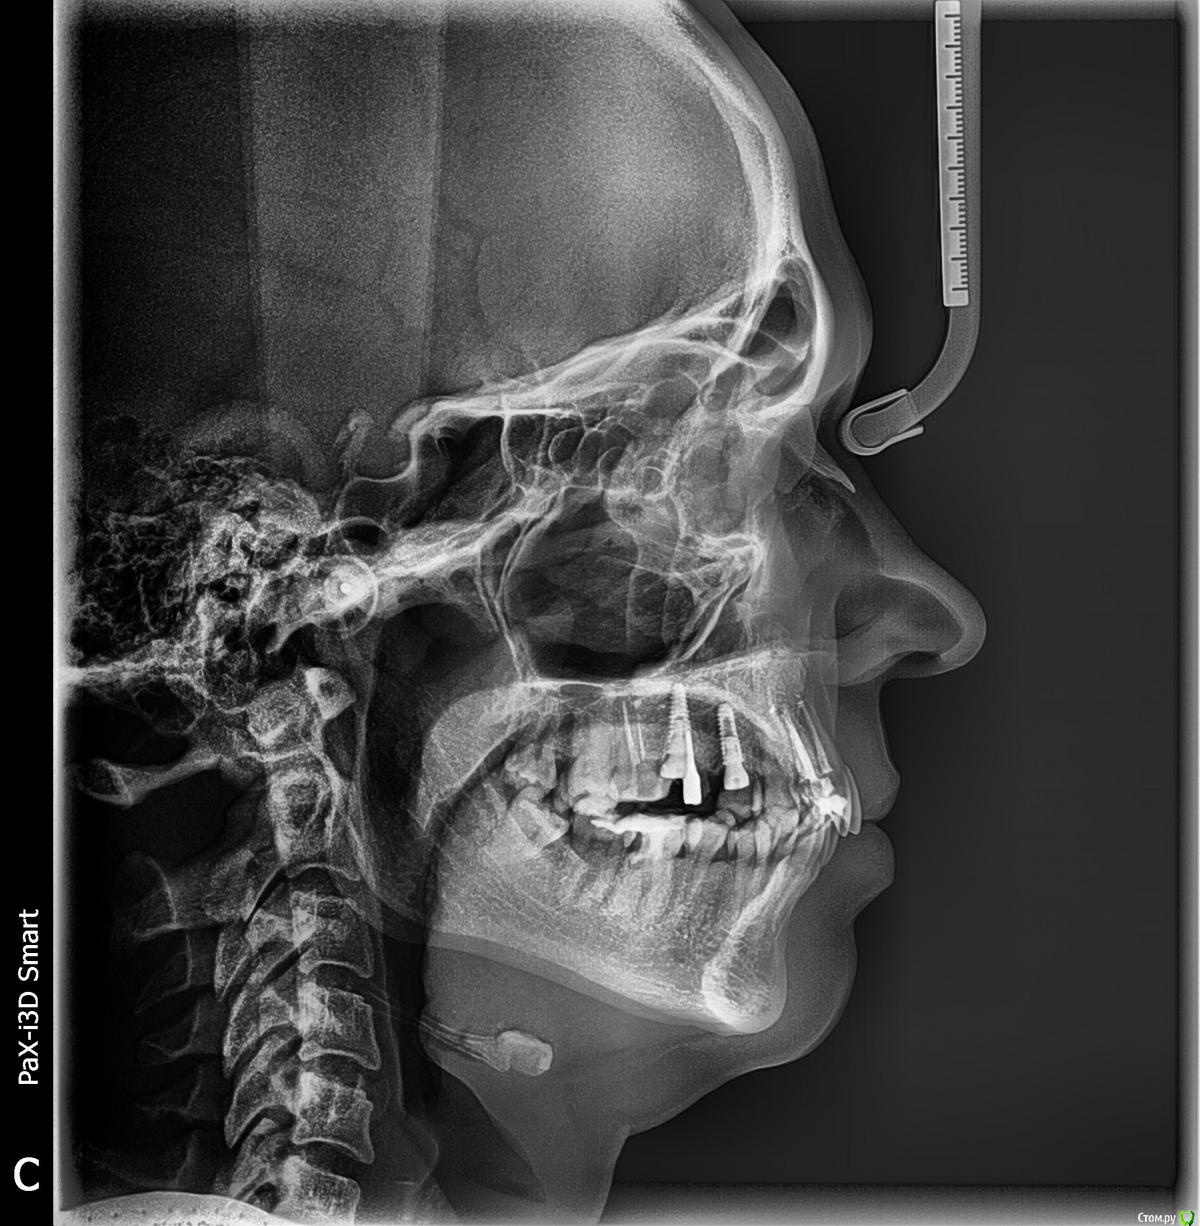

kamranchick Опубликовано 4 мая, 2018 Поделиться Опубликовано 4 мая, 2018 Добрый день Уважаемые коллеги, имеются проблемы с ортодонтией в нашем славном городе.Какие будут предложения по кейсу, сколько визитов и по ценникам, можно в личку.Пациент готов ездить в другие городаP.S пациент тоже будет следить за ходом этой ветки))) Ссылка на комментарий

krokomot Опубликовано 4 мая, 2018 Поделиться Опубликовано 4 мая, 2018 А импланты уже успели установить. 1 Ссылка на комментарий

kamranchick Опубликовано 4 мая, 2018 Автор Поделиться Опубликовано 4 мая, 2018 А импланты уже успели установить.Как видите вопросов много конечно, но что можно предложить имея такую картину. Ссылка на комментарий

krokomot Опубликовано 4 мая, 2018 Поделиться Опубликовано 4 мая, 2018 а снижение высоты есть? Ссылка на комментарий

kamranchick Опубликовано 4 мая, 2018 Автор Поделиться Опубликовано 4 мая, 2018 а снижение высоты есть?Ну углы рта опущены, модели не видел Ссылка на комментарий

krokomot Опубликовано 4 мая, 2018 Поделиться Опубликовано 4 мая, 2018 в данной ситуации конечно шляпа у пациента, если совсем все плохо, можно бы, ло бы просанировать для начала, снять скан, затем, поробовать на инвизилайнерах решить основные проблемы в окклюзии , затем тотальное протезирование. Идейка конечно не айс, но всё же выход. Ссылка на комментарий